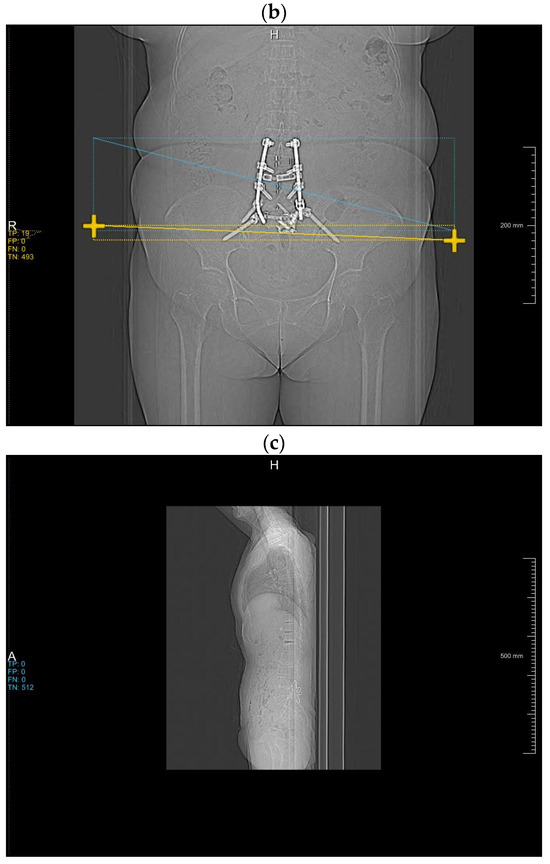

3.3. Impact on Reconstruction Time by Integrating the DLA

The DLA integration into the iMAR process allows for a reduction of reconstruction times (Figure 3). Simulation calculations on 1996 topograms, in which we included the result of our DLA, show that reconstruction times can be reduced to 72.6 ± 6.8% compared to the current iMAR reconstruction. In addition, the average reconstruction time in the group of patients with two metal implants is significantly reduced to 52.4 ± 6.1%, by iMAR reconstruction in one (fused) pass.

Figure 3.

Relative time-saving by implementing the DLA to iMAR reconstruction.

The curves depict the relative reconstruction time based on the proportion of metal along the z-axis for volumes containing only one metallic implant (hip or spine) and both metallic implants.